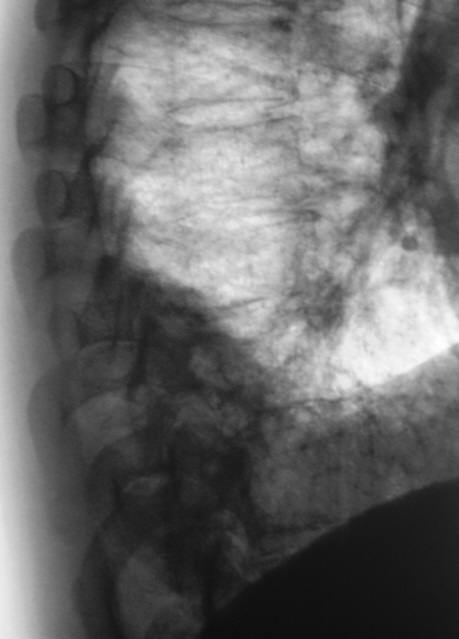

Сегодня произвели "очередной контроль". Произвели рентгенографию в прямой и правой боковой проекциях. Решили также произвести томографию в правой боковой проекции.

Катенёву В.Л.: На боковых томограммах, впечатление о инфильтрации с распадом в S10; томограммы, вероятно выполнены в положении лёжа, следовательо следует ожидать, что выпот растекся по грудной стенке и  не виден. С учётом характера распада, не исключаеиться туберкулёзный процесс.